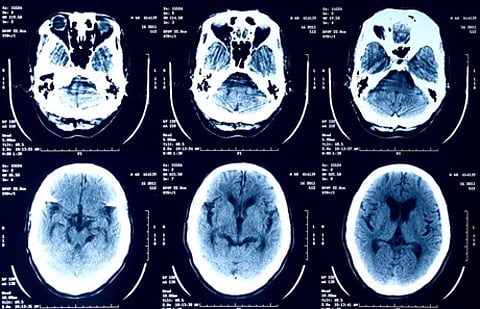

ومنذ أكتوبر الماضي، تم تشجيع المستخدمين على موقع التواصل الاجتماعي "X" على تحميل صور الأشعة السينية والتصوير بالرنين المغناطيسي وصور المسح الذري إلى روبوت الدردشة بالذكاء الاصطناعي "Grok" للمساعدة في تفسير نتائجهم.

وحسب "تك كرانش"، كان إيلون ماسك قد شجع مستخدمي "X" في منشور على تحميل صورهم الطبية إلى روبوت الدردشة "Grok"؛ لكن ماسك اعترف بأن النتائج من Grok "لا تزال في مرحلة مبكرة"؛ ولكن نموذج الذكاء الاصطناعي "سيصبح جيدًا للغاية".

وأوضح التقرير، من خلال مطالبة المستخدمين بتقديم صورهم الطبية إلى "Grok"، أن الهدف هو أن يتحسن نموذج الذكاء الاصطناعي بمرور الوقت، ويصبح قادرًا على تفسير الفحوصات الطبية بدقة متسقة. أما بالنسبة لمن لديه حق الوصول إلى بيانات "Grok" هذه؛ فليس من الواضح ذلك.